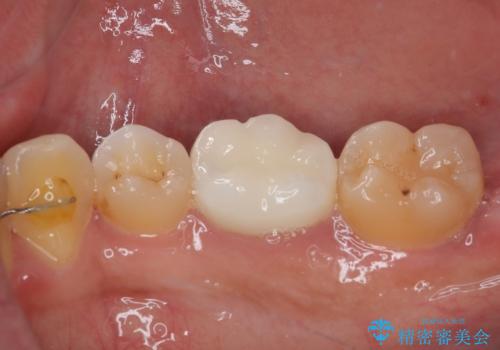

- 銀歯をセラミックにしたいとのことで来院された患者様です。検査の結果、メタルインレーが大きくご自身の歯の残る量を考慮して、オールセラミッククラウンによる補綴治療を行っていくことにしました。

拡大鏡視野下で、メタルインレー、虫歯の除去を行いオールセラミッククラウンに適した形に整えました。

違和感もなく、適合性も良い被せものを入れることができました。

適合の高い被せものを入れることにより再び虫歯になるリスクを下げることができます。